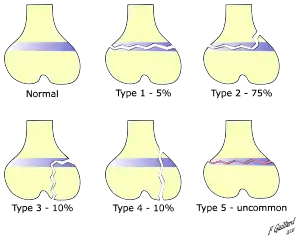

There are nine types of Salter–Harris fractures; types I to V as described by Robert B Salter and W Robert Harris in 1963,[3] and the rarer types VI to IX which have been added subsequently:[5]

• Type I – transverse fracture through the growth plate (also referred to as the "physis"):[6] 6% incidence

• Type II – A fracture through the growth plate and the metaphysis, sparing the epiphysis:[7] 75% incidence, takes approximately 12-90 weeks or more in the spine to heal.[8]

• Type III – A fracture through growth plate and epiphysis, sparing the metaphysis:[9] 8% incidence

• Type IV – A fracture through all three elements of the bone, the growth plate, metaphysis, and epiphysis:[10] 10% incidence

• Type V – A compression fracture of the growth plate (resulting in a decrease in the perceived space between the epiphysis and metaphysis on x-ray):[11] 1% incidence